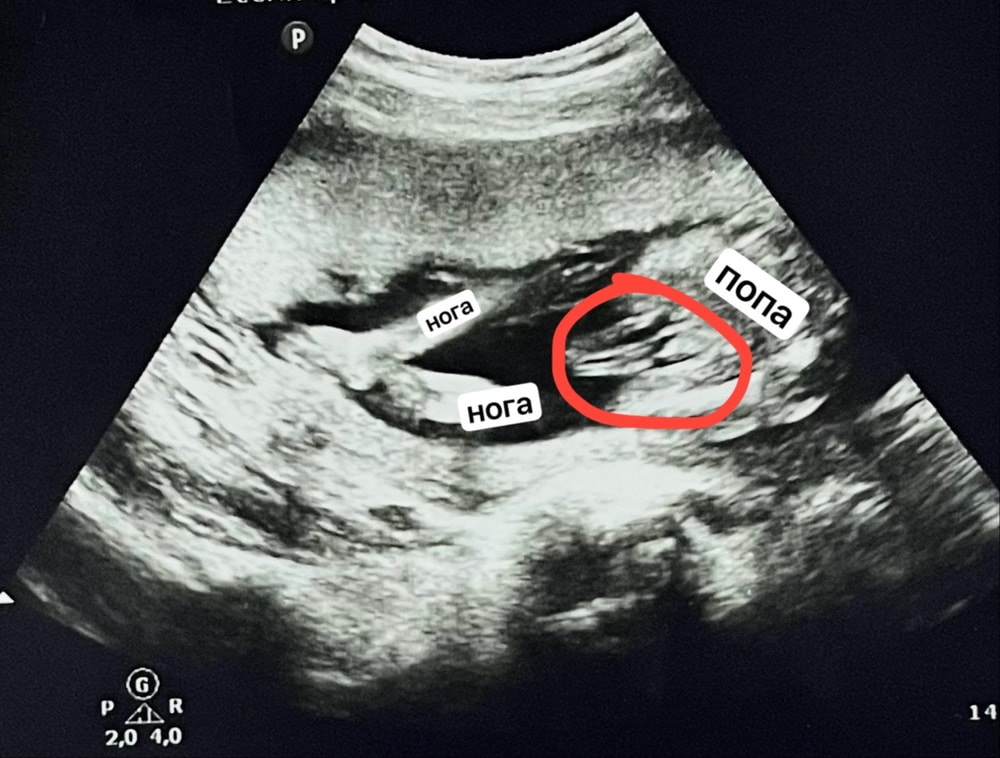

всем здравствуйте! недавно была на втором скрининге. На первом сказали, что у меня мальчик, а на втором - девочка. По фото узи у меня появились сомнения, потому что половой орган выпирает и не похож на девочку. Помогите определить)

Ariana Kravchenko, видео что это идёт продолжение ноги, кости. Соответственно чуть выше над вашим обеденным идёт писюн. А вот там под другим ракурсом надо посмотреть)

Ирина , пригляделась и увидела будто бы яички и выпуклость маленькую))

Между ножек вроде похоже на кофейное зёрнышко, я бы предположила девочку

Снимок не очень четкий, но вроде бы девочка. Выпирает не орган, а фрагмент пуповины.

Фото размазанное ,не особо понятно,но у девочек на узи тоже половые губы "выпирают"